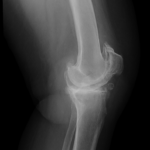

Your doctor will diagnose osteoarthritis based on the medical history, physical examination, and X-rays.

X-rays typically show a narrowing of the joint space in the arthritic knee.